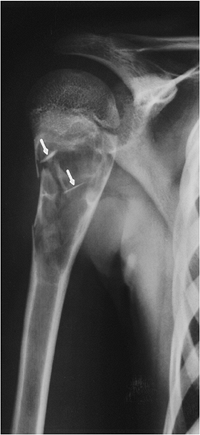

P.693

![]() |

|

FIGURE 10-33 Secondary chondrosarcoma. (A) AP radiograph of the pelvis showing an osteochondroma with fragmentation in the region of the cartilaginous cap (arrows). (B) CT image taken during biopsy confirms the thick cap (lines) with scattered osseous densities. Coronal T1-weighted (C) and axial T2-weighted (D) MR images showing the thick irregular cartilaginous cap, which is high signal intensity on the T2-weighted image (D) and low signal intensity on T1-weighted image (C).